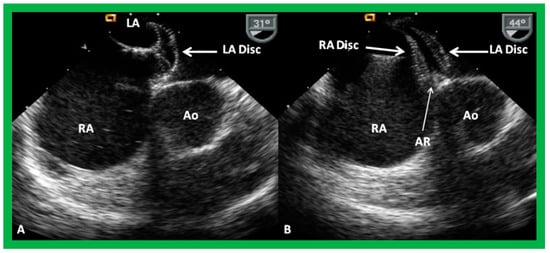

9.2. Device Position